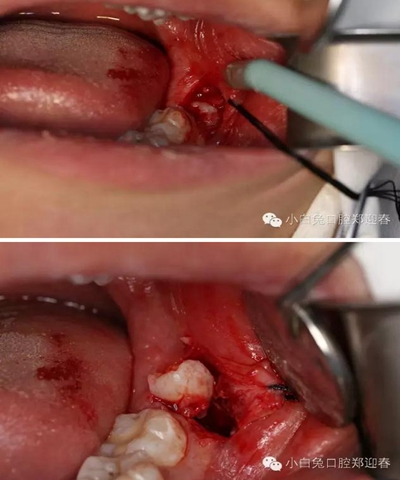

麻醉起效后,按照術(shù)前設(shè)計(jì),行粘膜切開翻瓣。

切口勿偏舌側(cè),頰側(cè)不要越過(guò)前庭溝,避免術(shù)后腫脹。

為了防止渦輪高速手機(jī)可能的組織纏繞,利用縫合線牽拉切開的瓣膜,充分暴露術(shù)區(qū)。

順著牙長(zhǎng)軸的方向挺出牙根,這樣可以避免因?yàn)檠栏D(zhuǎn)對(duì)神經(jīng)管的影響。

處理牙槽窩,保留完整的牙槽骨形態(tài)。

置入膠原蛋白,縫合創(chuàng)口。